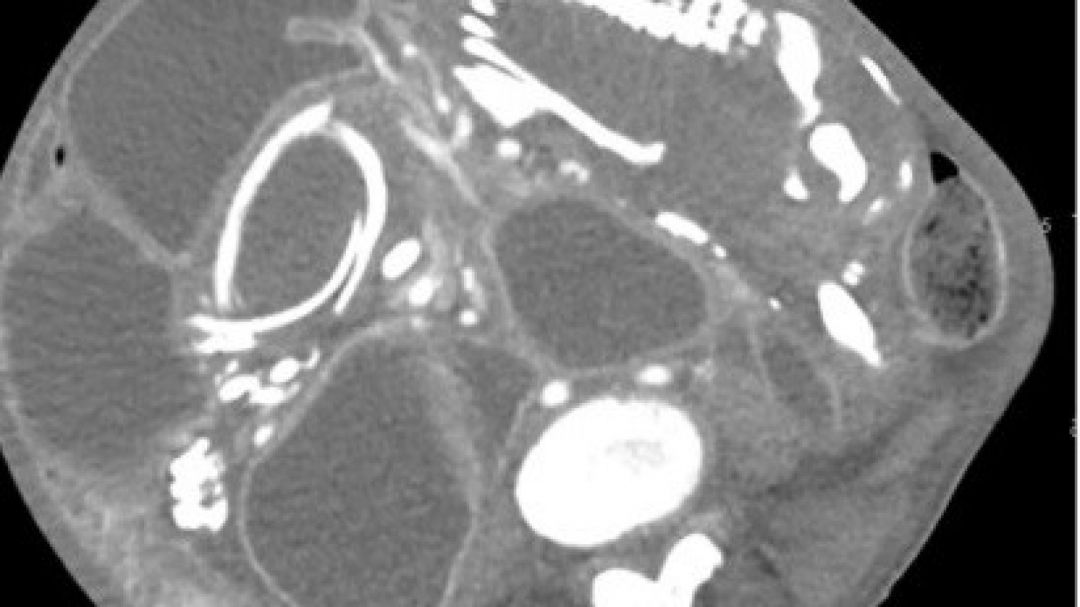

Crédito: Reprodução BMC Women's Health

O caso reportado no BMC Women's Health, revela que o feto comprimia os intestinos.

O feto desenvolveu membros superiores, ossos e até unhas. Seria o nono filho da mulher e parou de se desenvolver pelas 28 semanas.